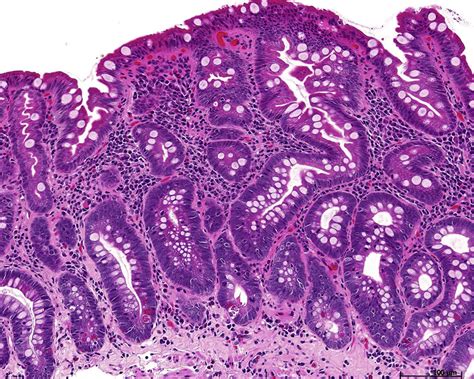

Receiving a diagnosis of Gastric Intestinal Metaplasia (GIM) can be understandably overwhelming, but understanding what it is and how it is managed is the first step toward effective care. Essentially, GIM is a condition where the normal cells lining the stomach are replaced by cells that more closely resemble those found in the intestines. While this transformation is not cancer, it is recognized as a potential precursor to gastric (stomach) cancer, making it a condition that requires proactive monitoring and management under the guidance of a gastroenterologist.

When a pathologist examines a biopsy sample, they may classify Gastric Intestinal Metaplasia into different types. These distinctions help doctors determine the potential risk profile of the condition.

Complete (Type I) The intestinal cells closely resemble the small intestine; generally considered lower risk.

Incomplete (Type II/III) The cells resemble those of the colon; these types are often associated with a slightly higher risk of progression.